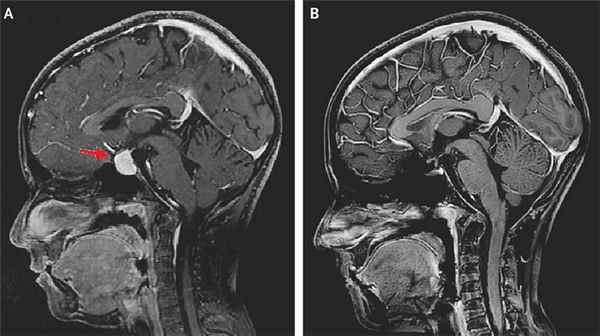

Диагностика аденомы гипофиза: тщательные гормональное и офтальмологическое обследования и нейровизуализация. Магнитно-резонансная томография — основной метод диагностики, позволяет выявить аденомы размерами менее 5 мм, однако, даже с учётом этого, примерно у 25–45% пациентов визуализировать аденому не удаётся. Компьютерную томографию применяют только в экстренных ситуациях при невозможности провести магнитно-резонансной томографии для исключения тяжёлых осложнений.

МРТ со срезами толщиной 1 мм

Вопрос об исключении опухоли гипофиза ставят при наличии головных болей, характерных расстройств зрения и эндокринопатии. Проводят нейровизуализационные исследования с толщиной среза 1 мм. МРТ более чувствительна, чем КТ, особенно для выявления микроаденом.